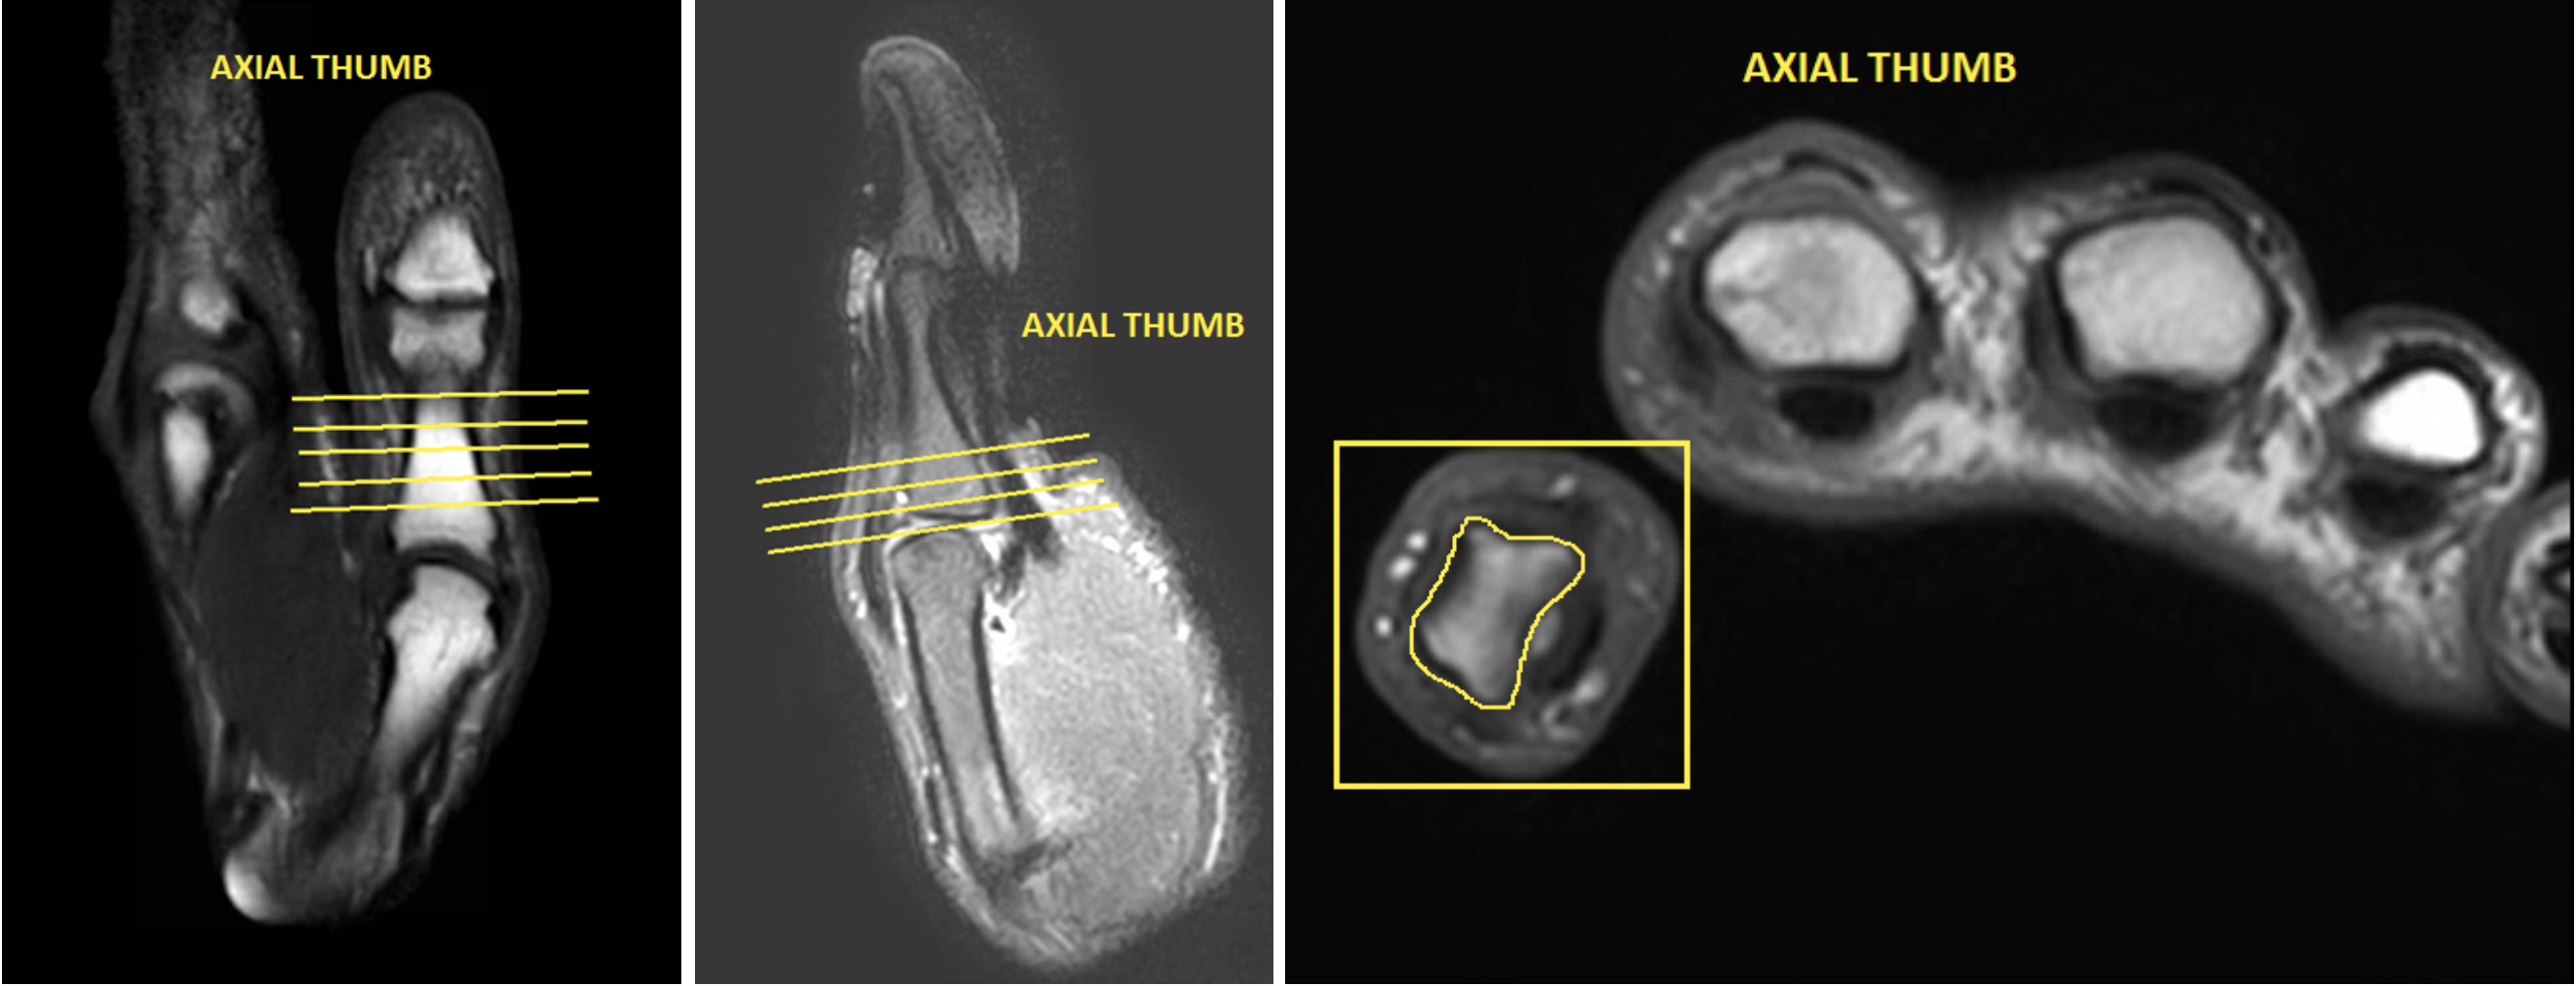

| AXIAL | T1 | TSE | 3mm | 0.5mm | None | 12cm | Cover area of interest |

| AXIAL | Mid TE (40-50) T2 Fat Sat | TSE | 3mm | 0.5mm | SPAIR | 12cm | Cover area of interest |

| AXIAL | T1 Fat Sat | TSE | 3mm | 0.5mm | SPIR | 12cm | same as pre |